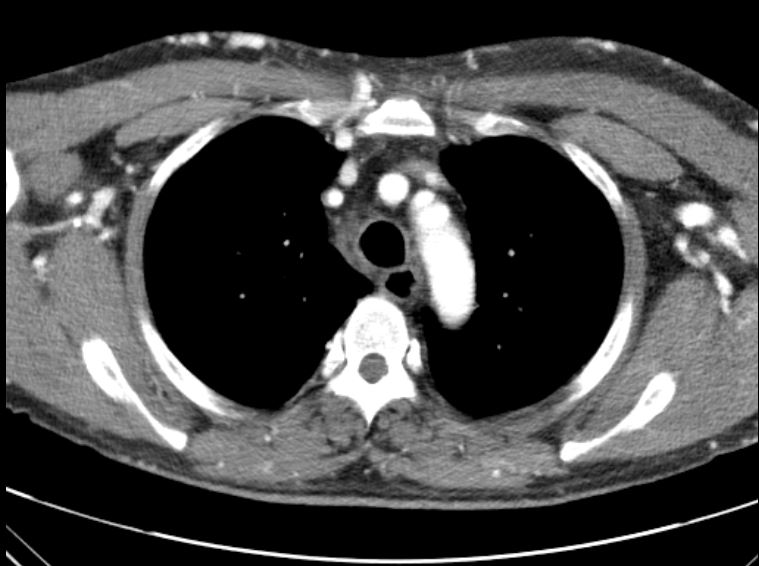

A 53-year-old man with type 2 diabetes, hypertension, COPD, and end-stage renal disease on hemodialysis presented with progressive facial swelling for one month. Vital signs were stable. Examination revealed a high-pitched voice, facial and bilateral upper limb swelling, and prominent chest wall venous engorgement. Chest CT showed bilateral brachiocephalic vein obstruction with multiple collaterals, consistent with superior vena cava (SVC) syndrome.

Relevant Test Results Prior to Catheterization

Chest CT revealed chronic thrombosis of the left brachiocephalic vein and a diminutive right brachiocephalic vein with multiple collateral channels, findings consistent with superior vena cava (SVC) syndrome secondary to chronic central venous obstruction.